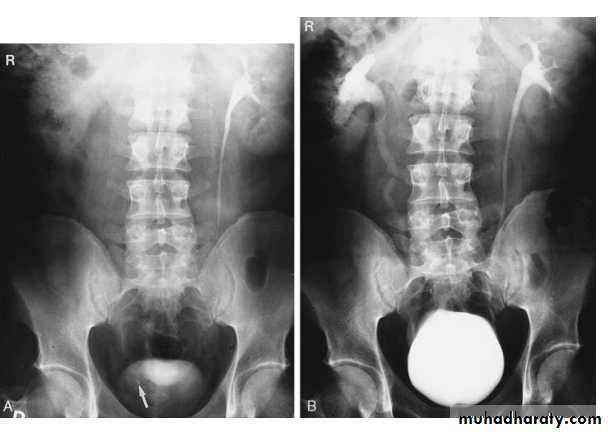

Pelvi-ureteric junction obstructionFilling defects

Multiple Calculi in the Renal Pelvis. A retrograde pyelogram demonstrates multiple filling defects

Radiograph from a retrograde pyelogram of the left kidney reveals a multilobulated filling defect (arrow) in the left renal pelvis. Biopsy confirmed transitional cell carcinoma.